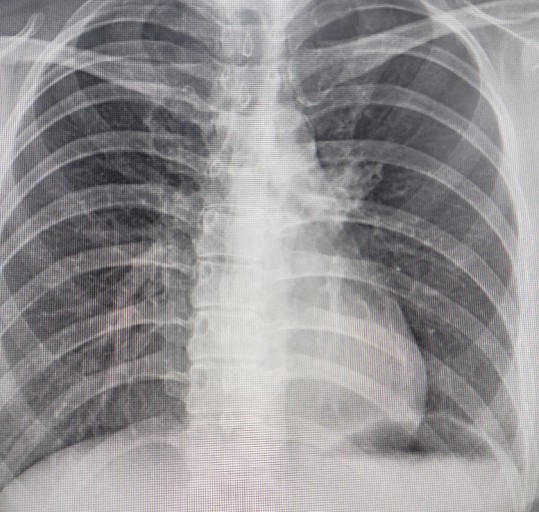

오늘은 단순한 감기와는 달리, 폐에 염증이 생기는 심각한 질환인 폐렴의 증상에 대해 이야기하려 합니다. 폐렴은 세균, 바이러스, 곰팡이 등 다양한 원인에 의해 발생하며, 특히 면역력이 약한 어린이나 노인에게 치명적일 수 있습니다.

폐렴은 보통 갑작스럽게 시작되며, 호흡기 증상과 함께 전신 증상이 복합적으로 나타납니다. 다음은 폐렴 환자들이 흔히 겪는 10가지 주요 증상입니다.